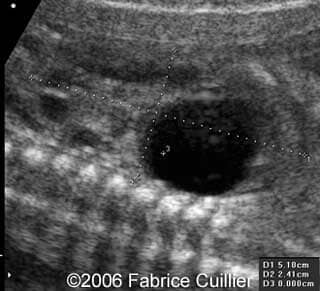

• an abnormal polycystic left kidney (34 X 17 mm) with an abnormal corticomedullar differentiation. This kidney was on the lumbar fossa.

Transverse view of the normal right kidney and the abnormal left kidney

Note the large cyst